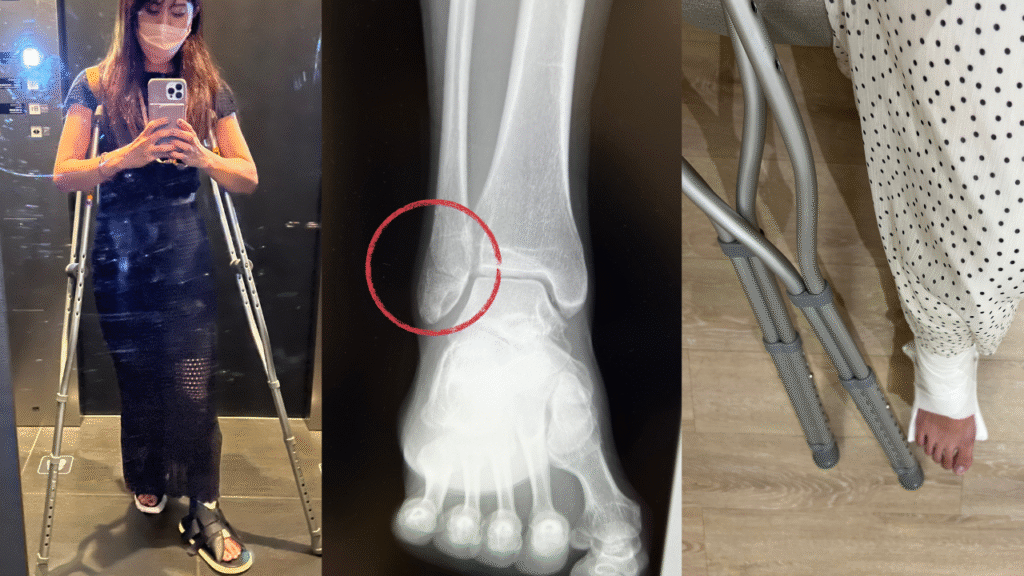

その結果、筋肉も栄養も不足していたのか、滑って転んだ拍子に骨折してしまったんです…。

松葉杖での生活はあっという間に筋肉を落とし、体の歪みや不調も出てきました。

さらに気持ちまで落ち込み、3ヶ月ほどで鬱っぽくなってしまったことも…。

この経験から「ただ痩せること」ではなく、体を整えて筋肉をつけることこそ大切だと強く実感しました。